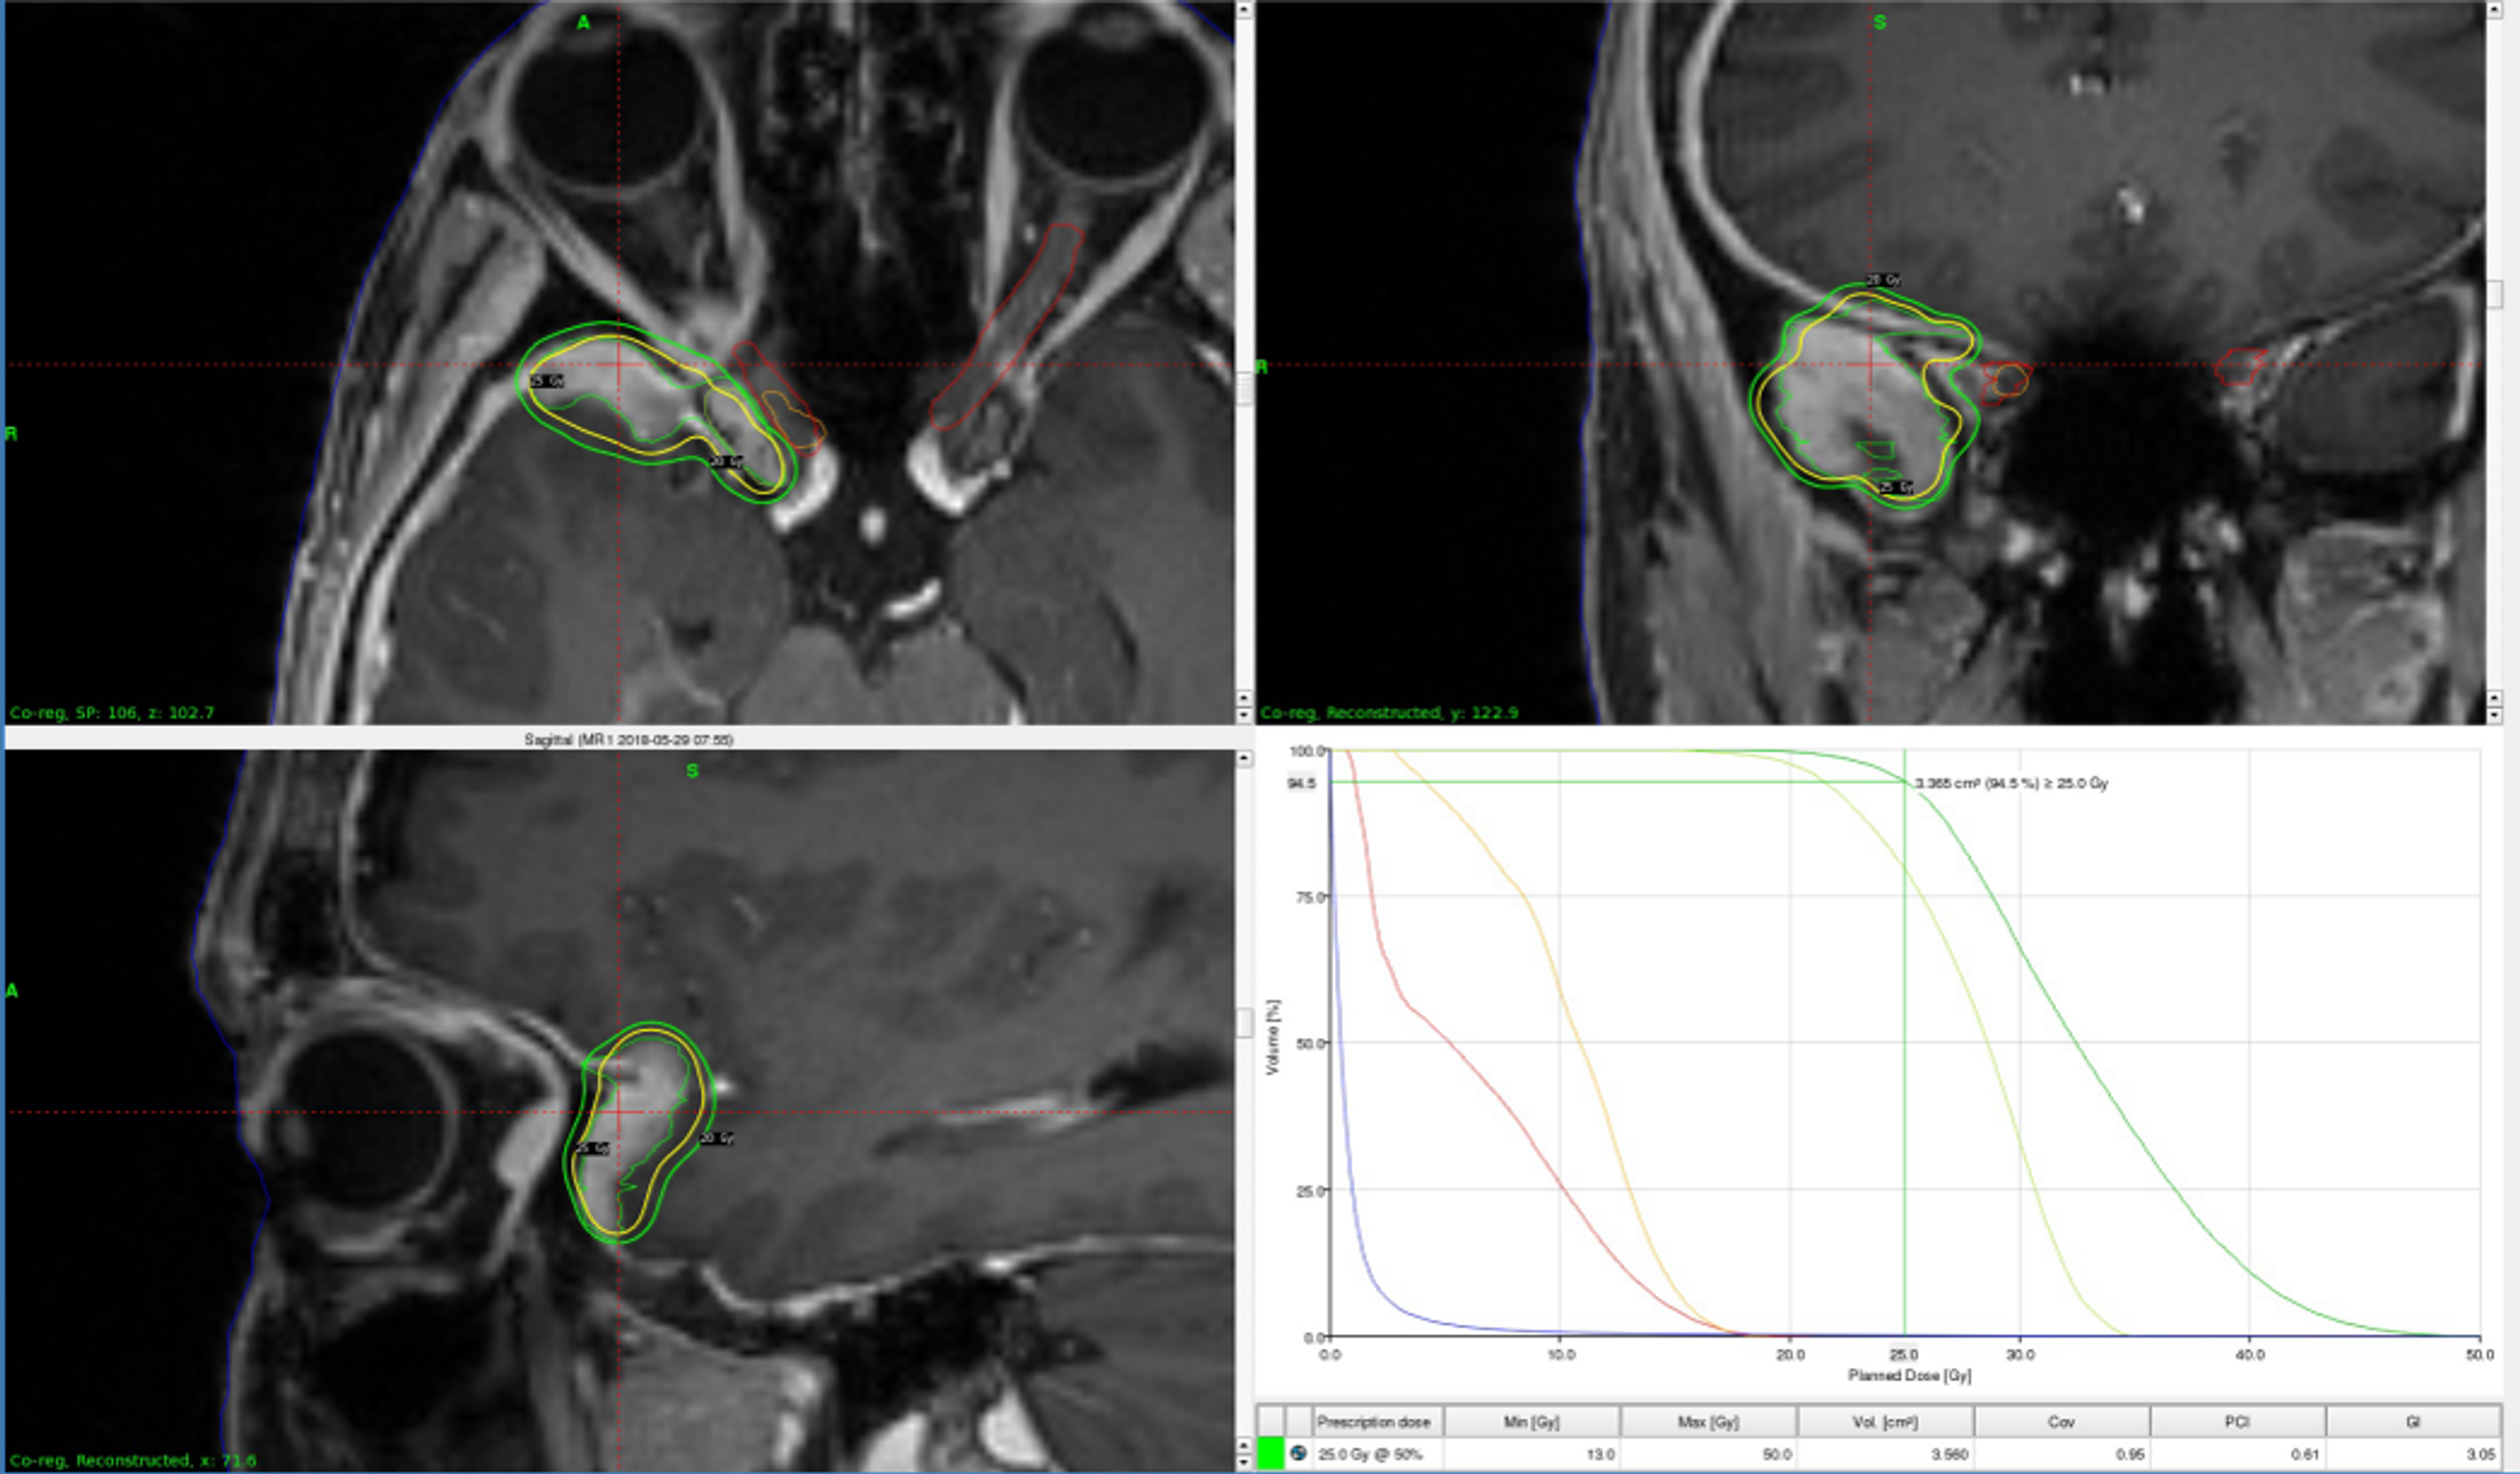

Source: cureus.com